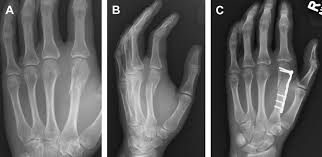

Upload Date: March 31, 2019 Full Size Image Dimensions: 322 × 157 Image Parent Post: Κατάγματα άνω άκρου

8a.Εσωτερική οστεοσύνθεση κατάγματος μετακαρπίου